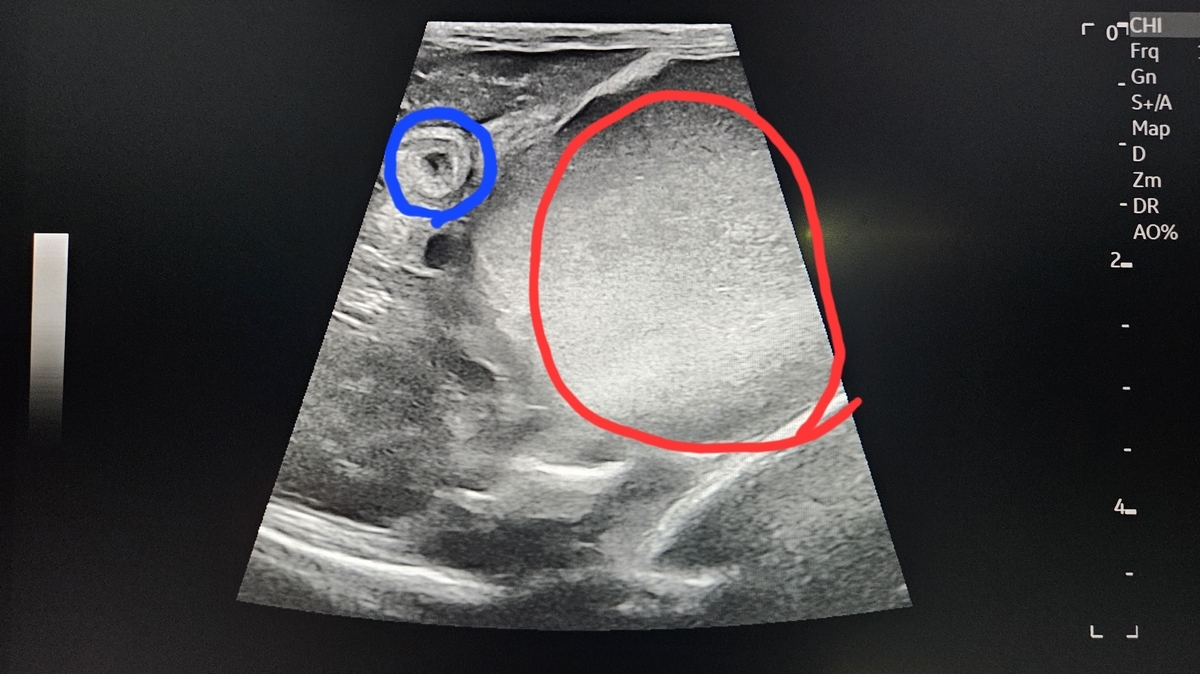

やはり 腸重積で間違いないとのことでした。黄色い丸の黒く映るのは腸液 ぺっちゃんこに映ってますが正常な形ではないそうです。

先天的に 機能してない部分があったのかもしれないね。とも青い丸のところが ろくの小腸を輪切りにした形で見えています

明らかな腸重積であると、尚且つ 内腔  粘膜  粘膜下層  筋層 漿膜(しょうまく)の小腸の5層構造内にも白い濁りで異常がみられます。赤丸=大きくなった胃